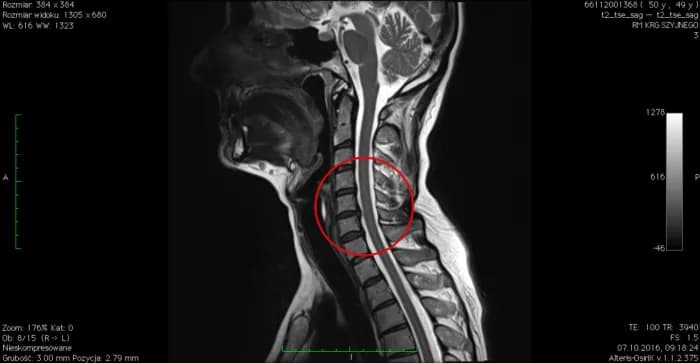

Rezonans magnetyczny (MRI) to złoty standard w diagnostyce przepukliny kręgosłupa szyjnego C6-C7. Pokazuje dokładny obraz tkanek miękkich, w tym dysków i nerwów. Pozwala precyzyjnie określić rozmiar i lokalizację przepukliny oraz stopień ucisku na struktury nerwowe.